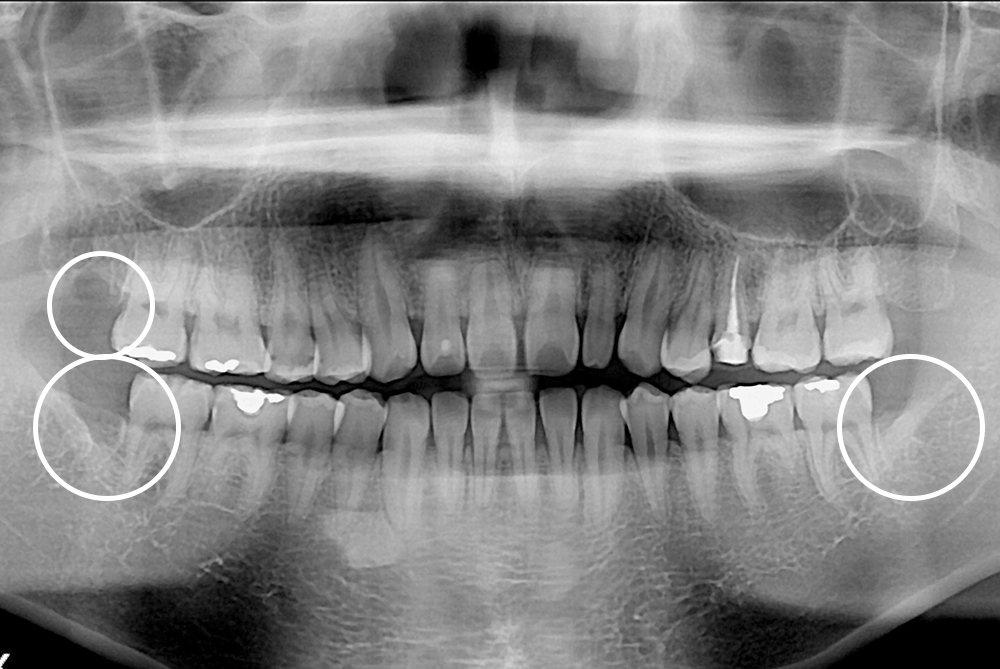

[사랑니] 매복 사랑니 발치

치료후 : 2019-08-09

세종치과는 구강악안면외과학 박사이신 원장님이 발치하는 치과입니다.